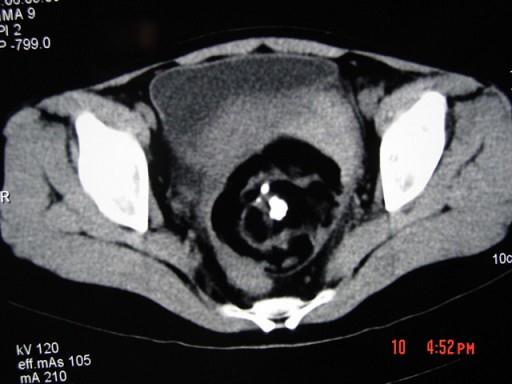

52岁女性患者,因下腹部胀痛就诊,B超提示:盆腔占位,行CT扫描,如图所示盆腔内见囊实性肿块,其内CT值不均,从-120至300hu不等,最可能的诊断为 ...

问题 52岁女性患者,因下腹部胀痛就诊,B超提示:盆腔占位,行CT扫描,如图所示盆腔内见囊实性肿块,其内CT值不均,从-120至300hu不等,最可能的诊断为 ( )

选项 A、卵巢囊肿 B、卵巢粘液瘤 C、盆腔结核 D、子宫肌瘤 E、盆腔畸胎瘤

答案 E